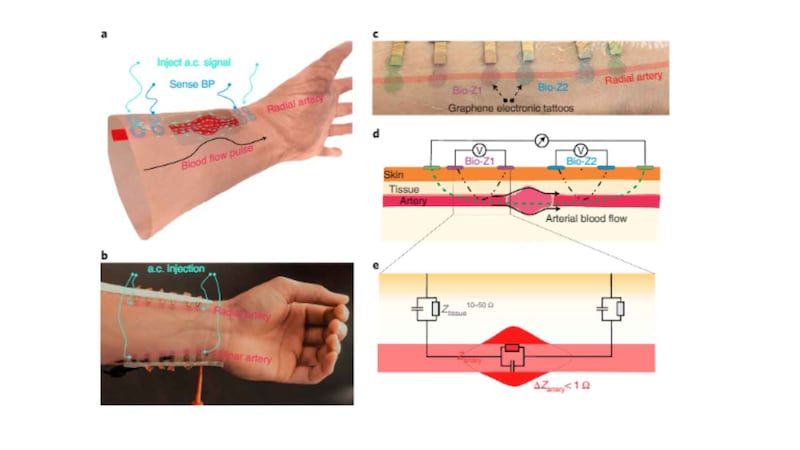

-Se adhiere al cuerpo del paciente, muy cerca de la muñeca.

-El dispositivo realiza sus mediciones disparando una corriente eléctrica en la piel y luego analizando la respuesta del cuerpo, conocida como bioimpedancia.

-Hay una correlación entre la bioimpedancia y los cambios en la presión arterial que está relacionada con los cambios en el volumen de sangre.

-La bioimpedancia puede convertirse en presión arterial mediante métodos de aprendizaje automático.

-El equipo tuvo que crear un modelo de aprendizaje automático para analizar la conexión y obtener lecturas precisas de la presión arterial.